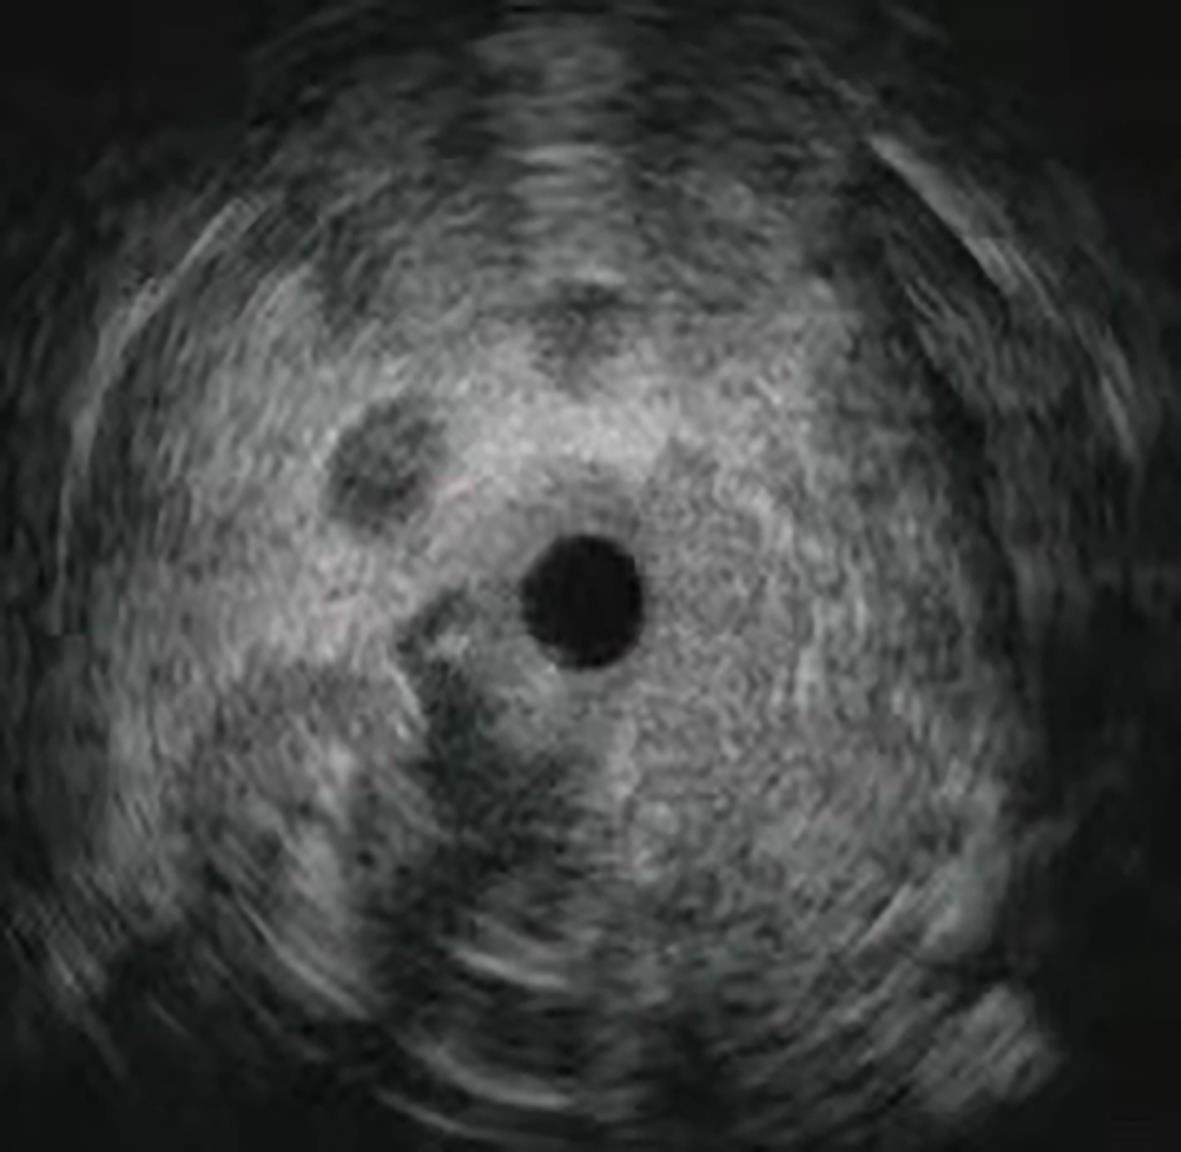

Application and development of endoscopic techniques in the diagnosis and treatment of liver diseases

Jingyi LU, Ying QU, Lungen LU

2024, 40(4): 834-838. DOI: 10.12449/JCH240431

Abstract(1359) HTML (315) PDF (641KB)(81)

Abstract:

Liver disease is one of the most important health problems around the world, and early diagnosis and timely intervention and treatment are the key to preventing liver-related morbidity and mortality rates. The development of endoscopic techniques has provided new diagnostic and intervention methods for liver diseases. This article reviews the application and development of endoscopic techniques in liver diseases from the following aspects: the technical advances and advantages of endoscopic ultrasound-guided liver biopsy; the application and development of endoscopic techniques in the treatment of portal hypertension caused by liver abscess/hepatic cyst and liver diseases, as well as interventional techniques in the treatment of liver tumors; the efficacy and prospects of the endoscopic techniques for weight loss, which are relatively new in China, in the treatment of nonalcoholic fatty liver disease/nonalcoholic steatohepatitis. Endoscopic techniques may hold promise for wide clinical application and exploration in in liver-related diseases in China, so as to provide more options for patients and doctors.